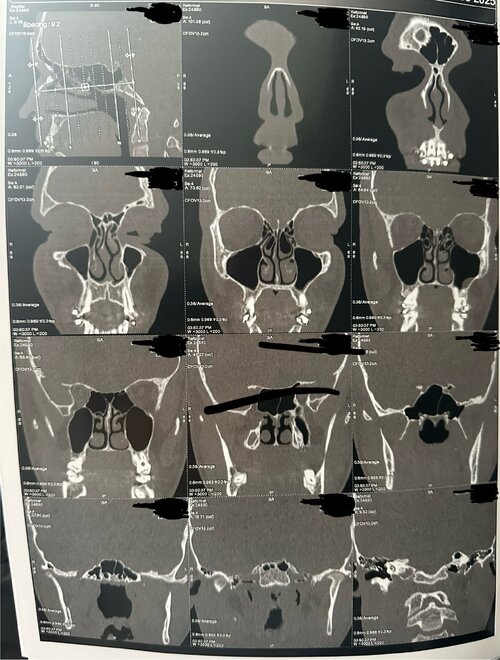

The CT scan provides a detailed view of the upper airway, nasal passages, and palate from multiple angles (axial, coronal, and sagittal). Based on the visible structures, several key anatomical features can be observed that relate to breathing efficiency, oral posture, and orthodontic development.

2. Nasal Airway

The nasal passages appear structurally clear, with no major obstruction or sinus blockage. The nasal septum seems mostly straight, though there may be a minor deviation toward one side in the lower portion. The inferior turbinates (soft tissue ridges inside the nasal cavity) show slight asymmetry, which is common and can contribute to uneven airflow between sides.

Because the palate forms the floor of the nasal cavity, a narrow palate typically reduces nasal base width. This can result in less efficient airflow through the nose, encouraging mouth breathing or snoring, especially during sleep. Expansion of the palate — if possible — can indirectly increase nasal volume, improving airflow and breathing comfort.

4. Palate Expander Considerations

Palatal expansion can serve both orthodontic and airway-improvement purposes. However, the type of expander that may be effective depends on suture maturity and growth potential.

An orthodontist would assess this alongside your bite, jaw alignment, and facial growth pattern. An ENT specialist might also evaluate nasal airflow, septal alignment, and turbinate size to determine if airway issues are contributing to any symptoms like congestion, mouth breathing, or snoring.

The CT scan provides a detailed view of the upper airway, nasal passages, and palate from multiple angles (axial, coronal, and sagittal). Based on the visible structures, several key anatomical features can be observed that relate to breathing efficiency, oral posture, and orthodontic development.

2. Nasal Airway

The nasal passages appear structurally clear, with no major obstruction or sinus blockage. The nasal septum seems mostly straight, though there may be a minor deviation toward one side in the lower portion. The inferior turbinates (soft tissue ridges inside the nasal cavity) show slight asymmetry, which is common and can contribute to uneven airflow between sides.

Because the palate forms the floor of the nasal cavity, a narrow palate typically reduces nasal base width. This can result in less efficient airflow through the nose, encouraging mouth breathing or snoring, especially during sleep. Expansion of the palate — if possible — can indirectly increase nasal volume, improving airflow and breathing comfort.

4. Palate Expander Considerations

Palatal expansion can serve both orthodontic and airway-improvement purposes. However, the type of expander that may be effective depends on suture maturity and growth potential.

- At age 16, the midpalatal suture is often partially or fully fused, which makes traditional expanders (RPE) less effective for skeletal change.

- More advanced techniques such as MARPE (Mini-Implant Assisted Rapid Palatal Expansion) or SARPE (Surgically Assisted Rapid Palatal Expansion) are typically used at this stage to achieve true bone widening rather than just dental tipping.

- Increased nasal airway space

- Improved nasal breathing

- Better tongue posture

- Broader upper arch for balanced occlusion

An orthodontist would assess this alongside your bite, jaw alignment, and facial growth pattern. An ENT specialist might also evaluate nasal airflow, septal alignment, and turbinate size to determine if airway issues are contributing to any symptoms like congestion, mouth breathing, or snoring.